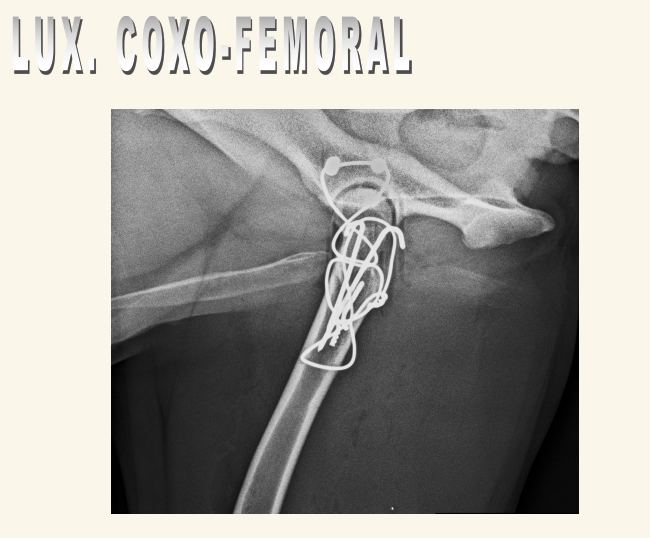

Luxación Coxo-femoral

- Por traumatismo, a veces leve si existe Displasia. Suele aparecer con fracturas de pelvis, uni o bilateral

- Normalmente cráneo-dorsal, aunque puede ser dorsal, ventral, caudal (rara) o intrapélvica

- Mejor 2 proyecciones pero en VD se ve mejor (ilion desplazado, mayor tamaño articular, perdida de contorno liso)

- Tambien hay luxacion sacro iliaca.

- Hay que ver la direccion de la luxacion. La mas frecuente es craneo-dorsal pero hay mas.